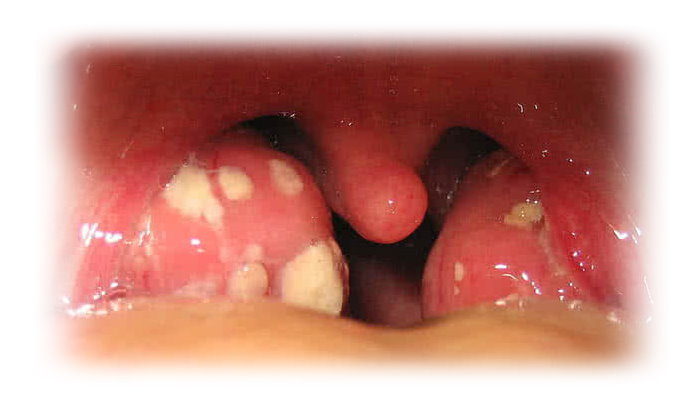

هل تعاني من وجود نقاط مؤلمة صفراء أو بيضاء بداخل فمك أو في نهاية حلقك؟